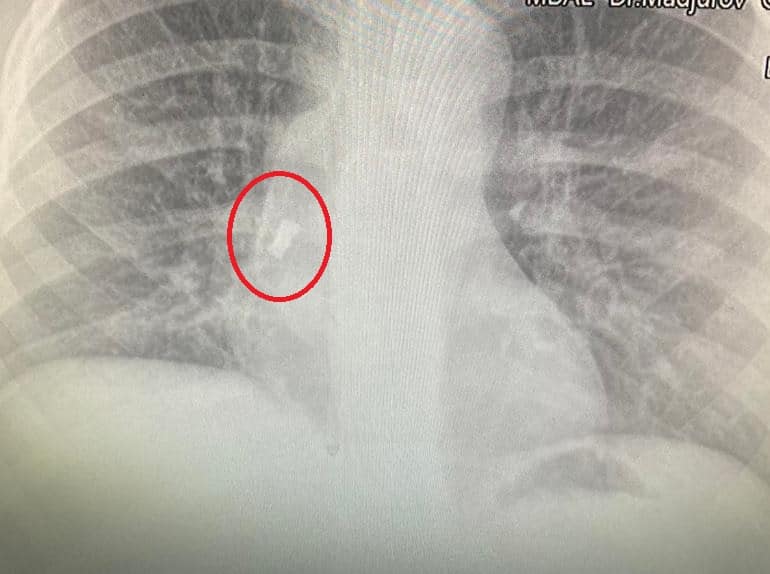

След известно време синът й започва да вдига температура, лекуван е с антибиотици, но температурата продължава. Личният лекар назначава рентгеново изследване и на снимката се вижда зъбът. От него се е развила инфекция на дихателните пътища, което обяснява повишената температура. Момчето е прието по спешност, операцията е извършена почти веднага от УНГ-специалистите доц. д-р Даниел Петков, д-р Ивайло Илиев и анестезиолога д-р Антон Григоров.